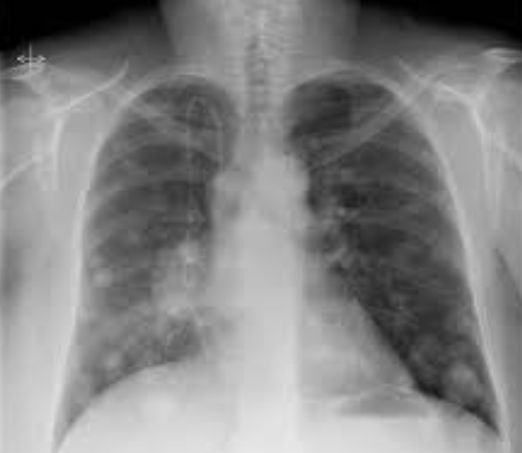

Αμφοτερόπλευροι πνευμονικοί όζοι ενδεικτικοί μεταστάσεων μελανώματος (Ευγενική παραχώρηση Dr. V. Penopoulos)